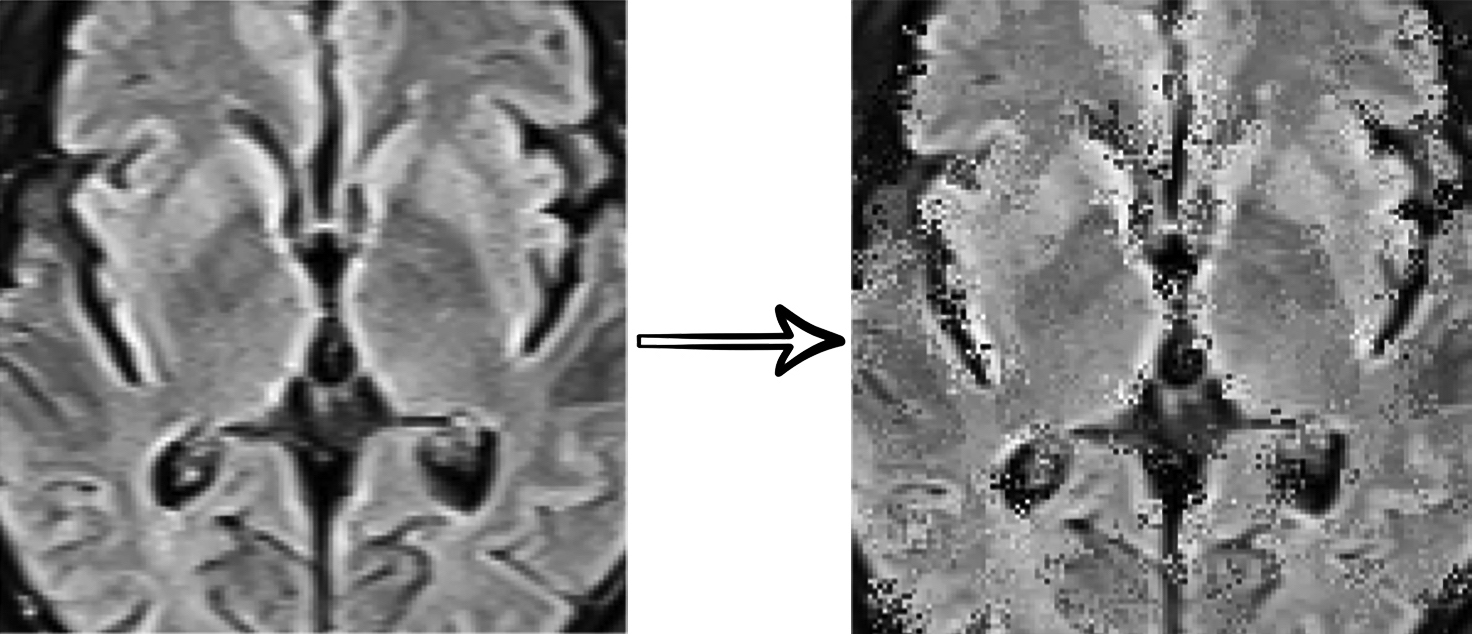

In this work, we use a self-supervised learning method to extract specific features of our data from multiple perspectives (appearance, texture, context, etc.) by combining three different supervision tasks that were proposed in “Models Genesis” [31]. Our model consists of a U-Net [25] with a ResNet [9] encoder. Each supervision task consists of a particular transformation and reconstructing the original image from the transformed one (see Fig. 3). Finally, the encoder part of the network is fine-tuned for the target classification task.

In this document, we provide additional materials to supplement our main submission. In the first section, the dataset which is provided and used for this paper is investigated. In the second section, we provide the mathematical details of Otsu Thresholding[23], which is used in pre-processing step. Third section illustrates four examples of our self-supervised training.

5.3 Self-Supervised Training Results Visualization